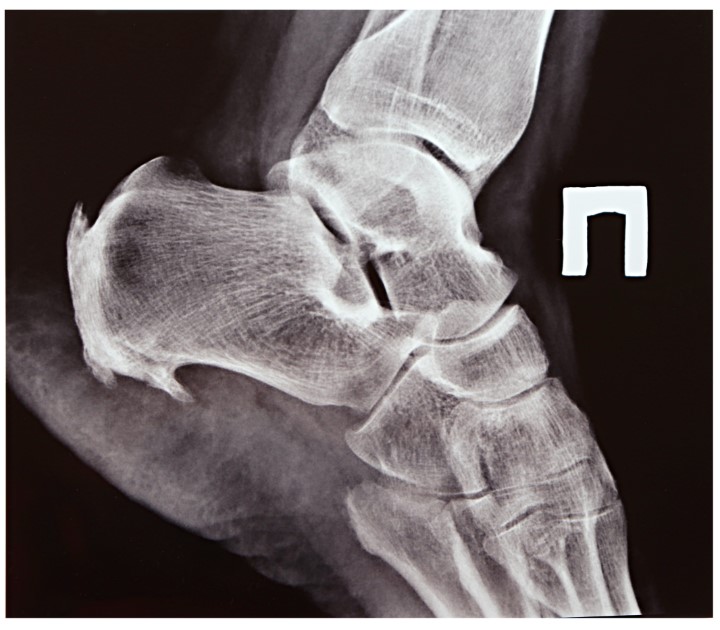

The appearance of your heel might help your doctor diagnose Haglund's deformity. In the event that your doctor suspects you have Haglund's deformity, they may order an X-ray of your heel bone. Your doctor can then determine if you have the prominent heel bone.